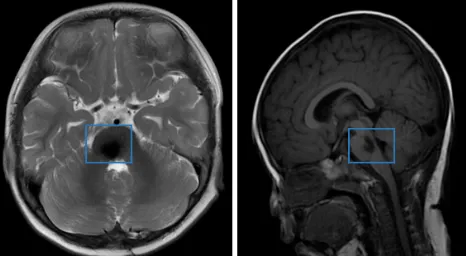

滿懷的忐忑,在看到急診醫(yī)生面露難色后全都化作了實體。MRI檢查結(jié)果顯示:第四腦室底部占位性病變。

影像